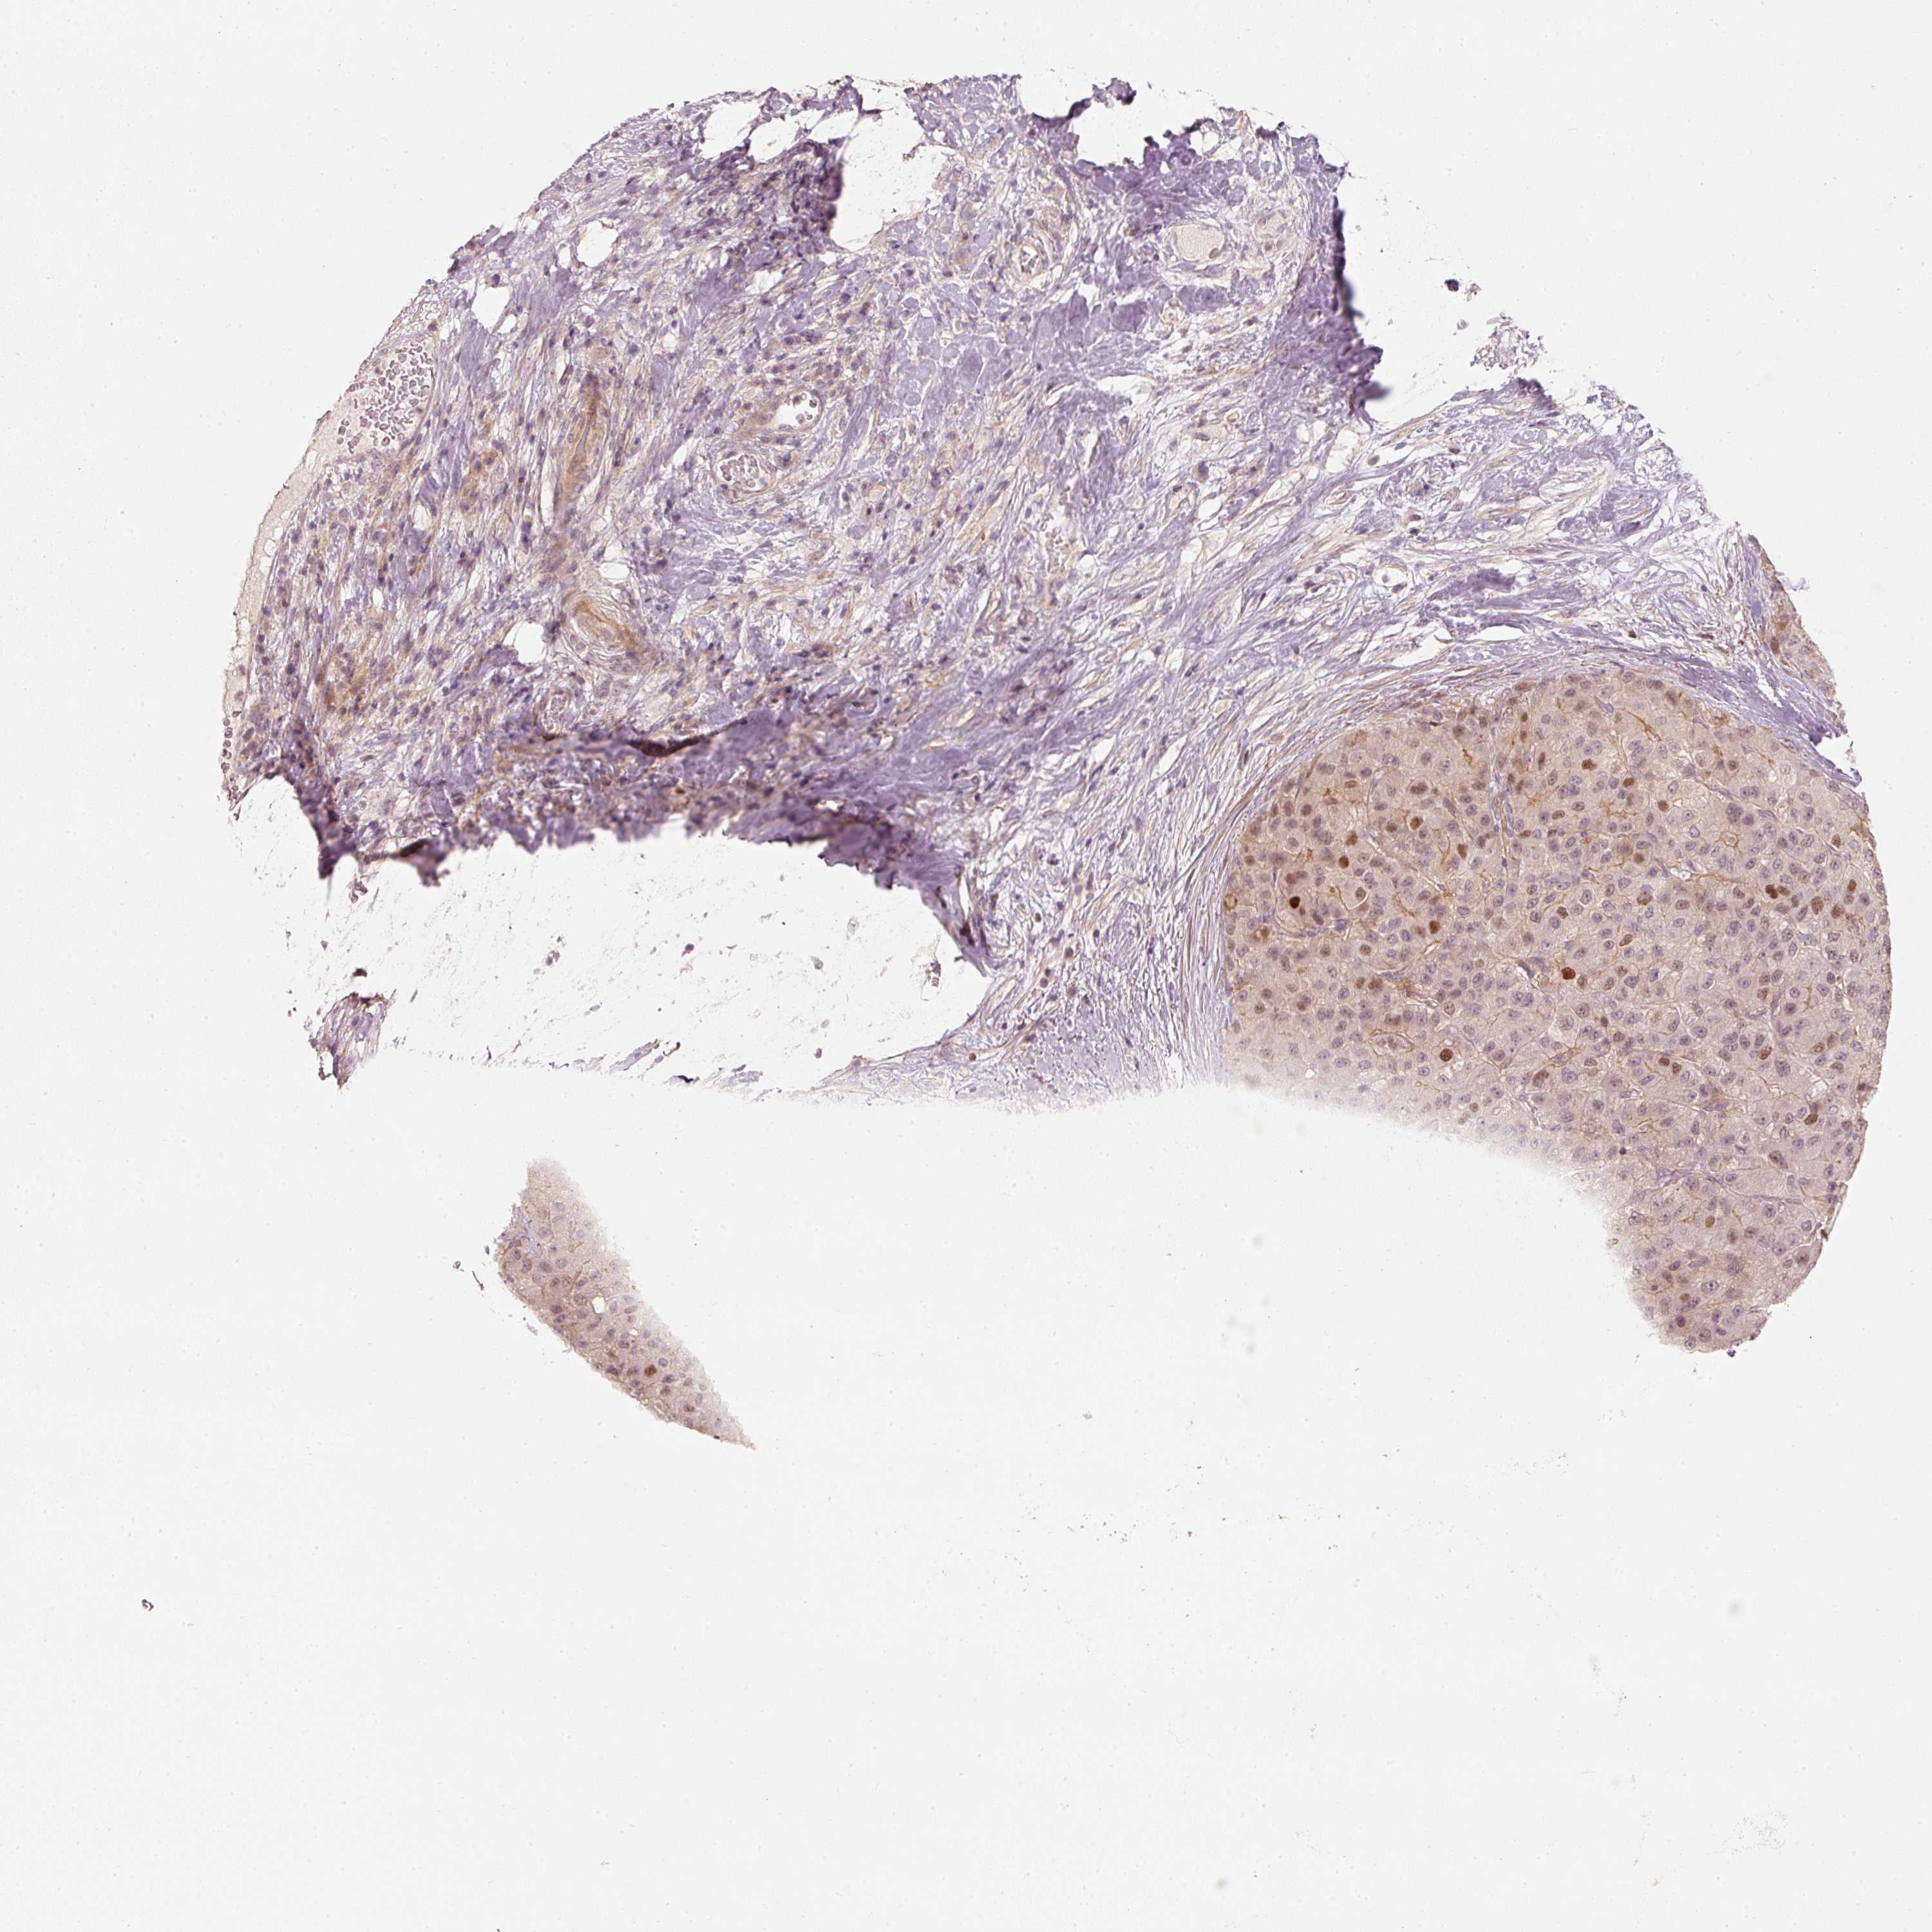

LIVER CANCER - Protein expressioni

A mouse-over function shows sample information and annotation data. Click on an image to view it in a full screen mode. Samples can be filtered based on level of antibody staining by selecting one or several of the following categories: high, medium, low and not detected. The assay and annotation is described here.

Note that samples used for immunohistochemistry by the Human Protein Atlas do not correspond to samples in the TCGA dataset.

Antibody stainingi

Antibody staining in the annotated cell types in the current human tissue is reported as not detected, low, medium, or high, based on conventional immunohistochemistry profiling in selected tissues. This score is based on the combination of the staining intensity and fraction of stained cells.

Each image is clickable and will lead to virtual microscopy that enables deeper exploration of all samples and also displays staining intensity scores, fraction scores and subcellular localization as well as patient and tissue information for each sample.

Antibody HPA054060

Staining

High

Medium

Low

Not detected

Intensity

Strong

Moderate

Weak

Negative

Quantity

>75%

75%-25%

<25%

None

Location

Nuclear

Cytoplasmic/membranous

Cytoplasmic/membranous,nuclear

Cholangiocarcinoma

Carcinoma, Hepatocellular, NOS